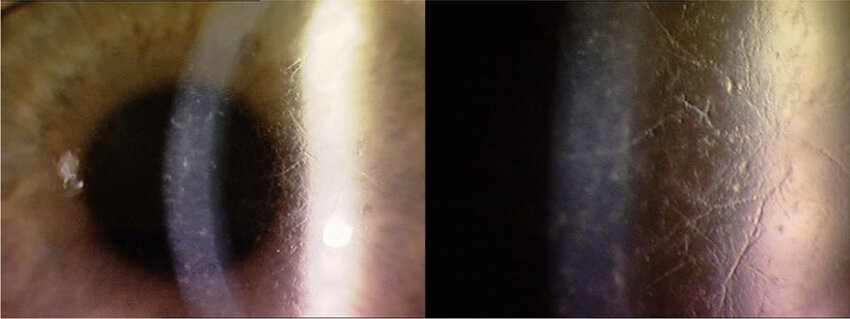

type II 격자이상증은 Meretoja's syndrome 이라 불리는데,

Familial amyloid polyneuropathy type IV 에 해당합니다.

이는 상염색에 열성이며,

가족성의 전신적인 아밀로이드증이 나타나는 질환의 한 형태로,

20세 이후에 나타나게되며, 진행성의 뇌신경 및 말초 신경 마비,

건조한 피부, 튀어나온 입술 등의 전신증상이 동반되는 것이 특징입니다.

소량의 굵은 선이 보이며, 각막 진무름은 드물게 나타납니다.